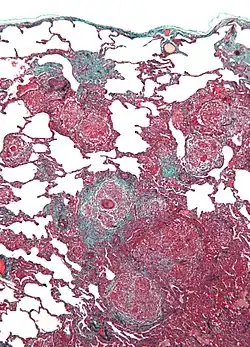

Als Vogelhalterlunge (auch: Vogelzüchterlunge oder Taubenzüchterkrankheit) wird eine Alveolitis exogen-allergischer Ursache bezeichnet. Sie kann in akuter oder in schleichend-chronischer Form auftreten.

Bei den Allergenen, die diese Krankheit auslösen, handelt es sich um tierische Proteine, die im Staub und Kot von Vögeln auftreten. Federn in Daunen-Textilien kommen ebenfalls in Frage. Diese Allergene führen zu einer entzündlichen Reaktion des Lungengewebes, die durch eine Immunkomplexreaktion vom Typ III verursacht wird.

Die Symptome klingen meist innerhalb weniger Tage wieder ab. Bei andauerndem Allergenkontakt kann das Lungengewebe stark beschädigt oder zerstört werden. Die Lungenfunktion kann dauerhaft eingeschränkt sein. In Einzelfällen wird auch das Herz belastet.